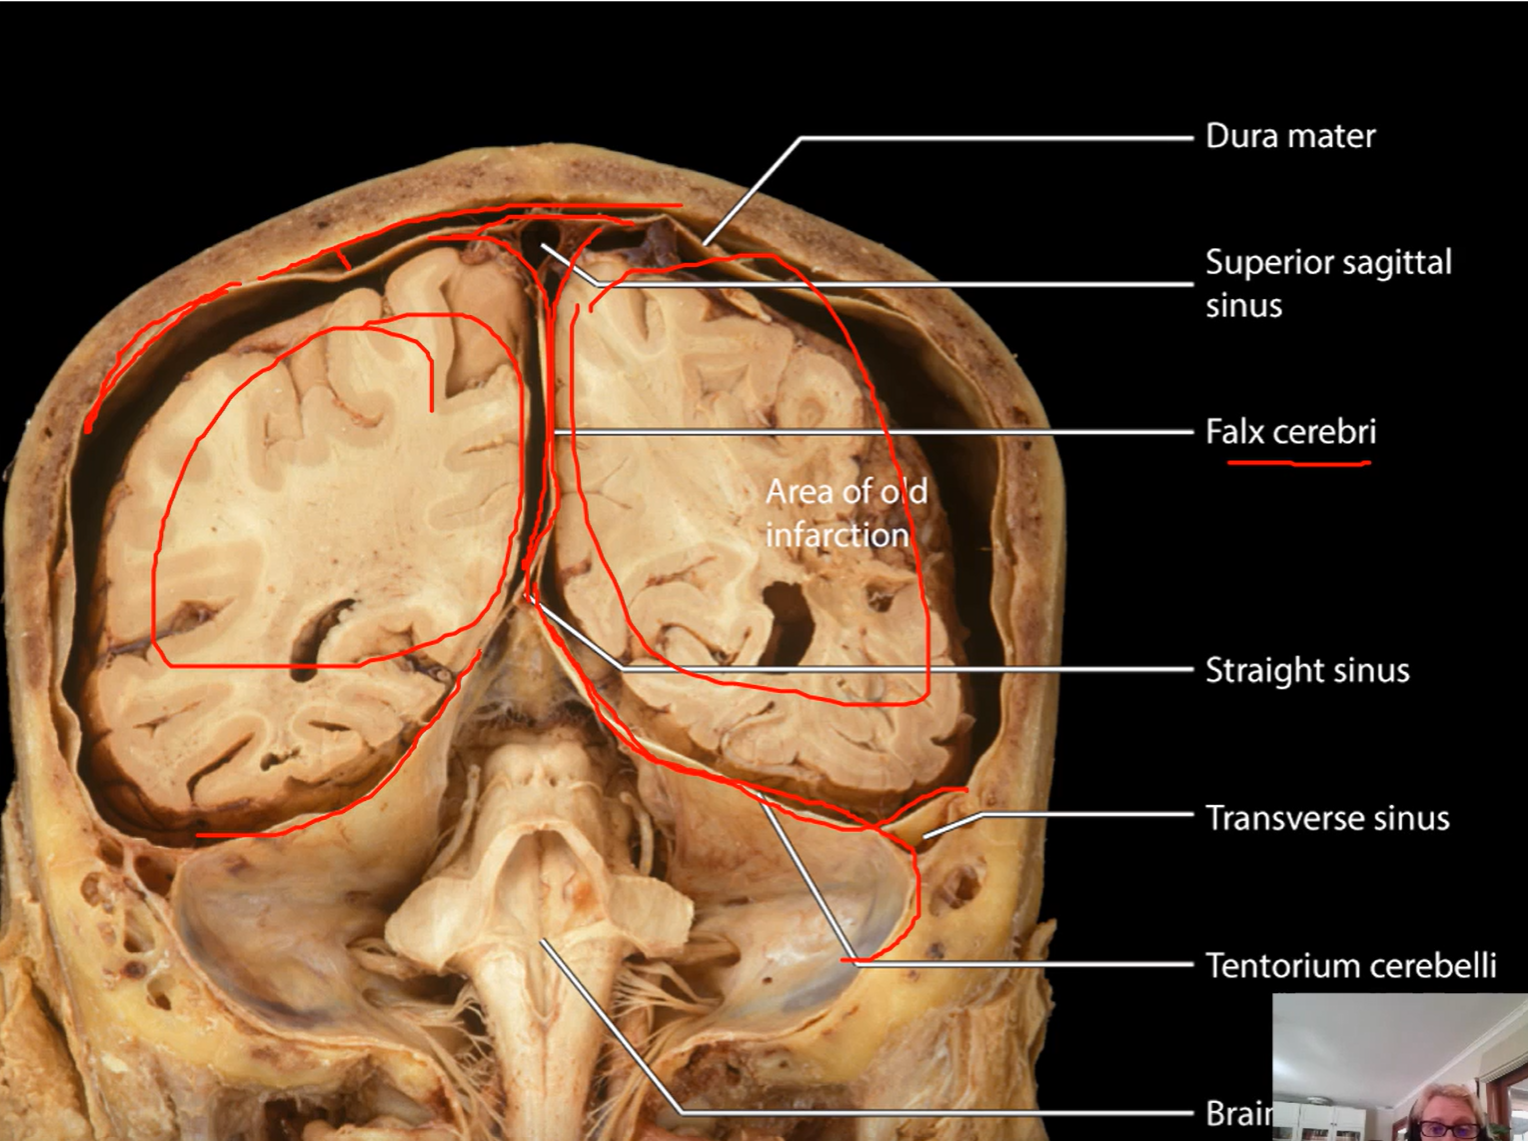

What separates the cerebral hemispheres and cerebellum from cerebrum?

Dural folds

What is being drawn over in red?

Dural folds

What lies between meningeal dura mater and periosteal dura mater?

Dural venous sinuses